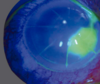

111

Dx

Queratocono con estrias de Vogt

112